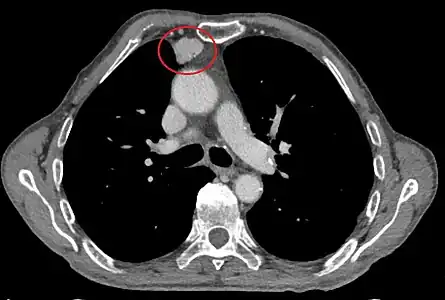

- Aspect scannographique

Présentation tomodensitométrique classique d'un thymome à un stade précoce (cercle rouge). À l'arrière, l'aorte, la veine cave supérieure et l'artère pulmonaire sont visibles en coupe.